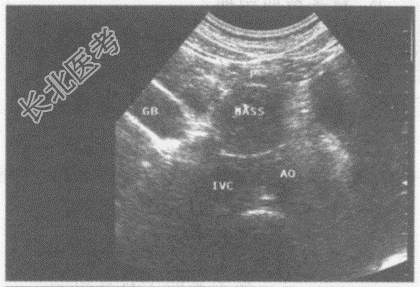

超声综合描述: 腹主动脉下腔静脉前方,胰头右侧可见3.6cm×3.4cm圆形低回声区, 边界清晰,包膜完整, 内回声尚均匀,CDFI: 内未明显血流信号,周边可见血管绕行。见下图及彩图。